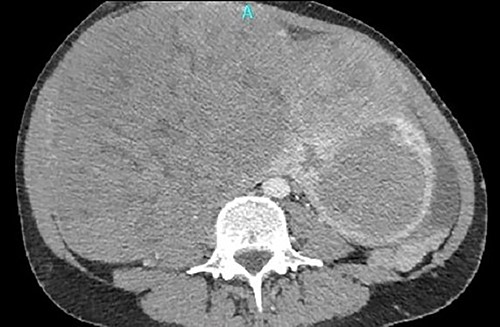

One month later, after vascular consultation, a chest and pelvis computed tomography angiography was performed and a huge mass originating from the uterine wall was revealed (26 cm in diameter) (Fig. 1). The mass compressed the surrounding organs, especially IVC (Fig. 2). Furthermore, thrombosis of left femoral and external and common iliac veins, as well as infrarenal IVC patency (without clarification of IVC thrombosis), was detected. The common, internal and external right iliac veins were patent, and no PE was detected.

A huge mass originating from the uterine wall was revealed after pelvis CTA.

Thrombosis of left femoral and external and common iliac veins.